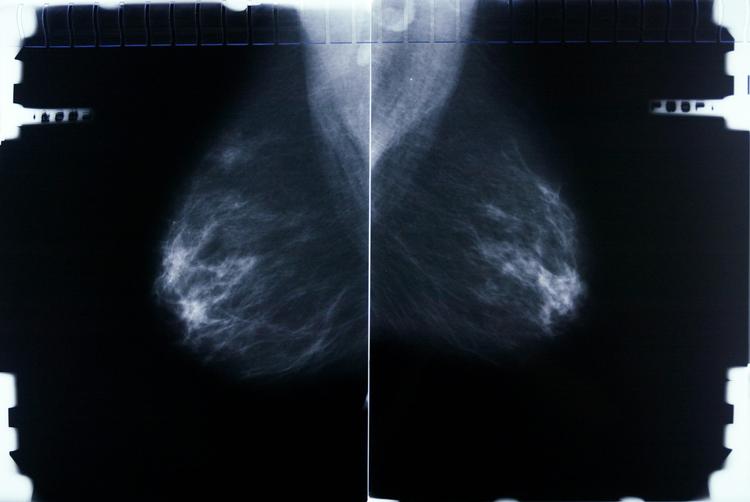

Kvinder, der bliver undersøgt for brystkræft på Rigshospitalet, bliver sendt hele vejen til Aabenraa for at få svar på, om deres knuder er godartede eller ondartede.

Det er konsekvensen af, at Rigshospitalet ikke længere kan undersøge kvinderne inden for de tidsfrister, der gælder.